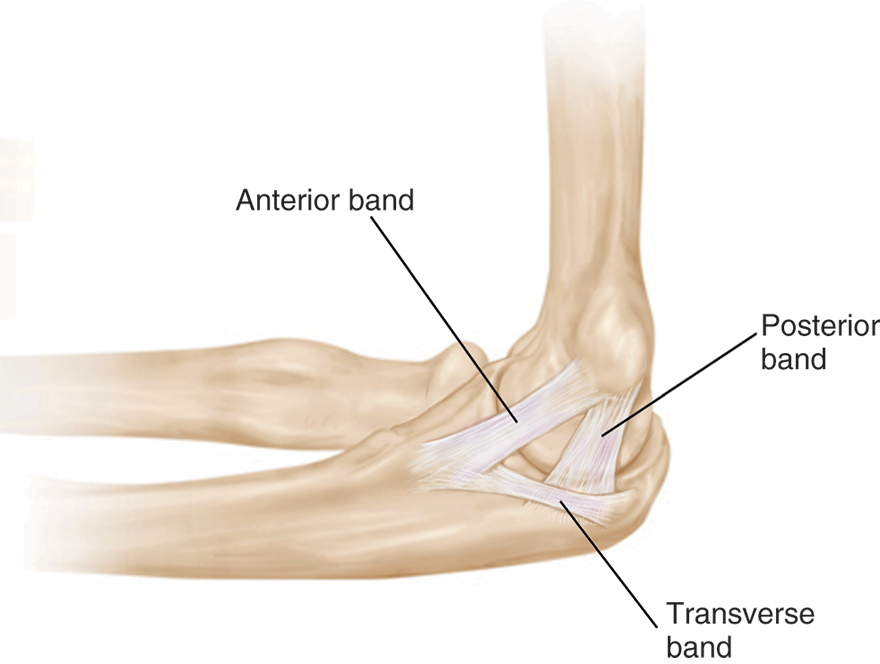

The ulnar collateral ligament is a thick band of tissue on the inside part of the elbow that is meant to resist the strong forces involved in overhead throwing. The ligament, which connects the humerus to the ulna, is actually made up of three separate, connected bands:

• The anterior (front) band. This is the most important structure in providing stability to overhead throwing athletes.

• The posterior (back) band.

• The transverse band, which connects the other two bands.

This illustration of the inside part of the elbow shows the three bands that make up the ulnar collateral ligament (UCL).

Reproduced from Gramstad M: Anatomy of the shoulder, arm, and elbow, in Lieberman JR, ed: AAOS Comprehensive Orthopaedic Review, ed 3. Rosemont, IL, American Academy of Orthopaedic Surgeons, 2020, pp 715-726.